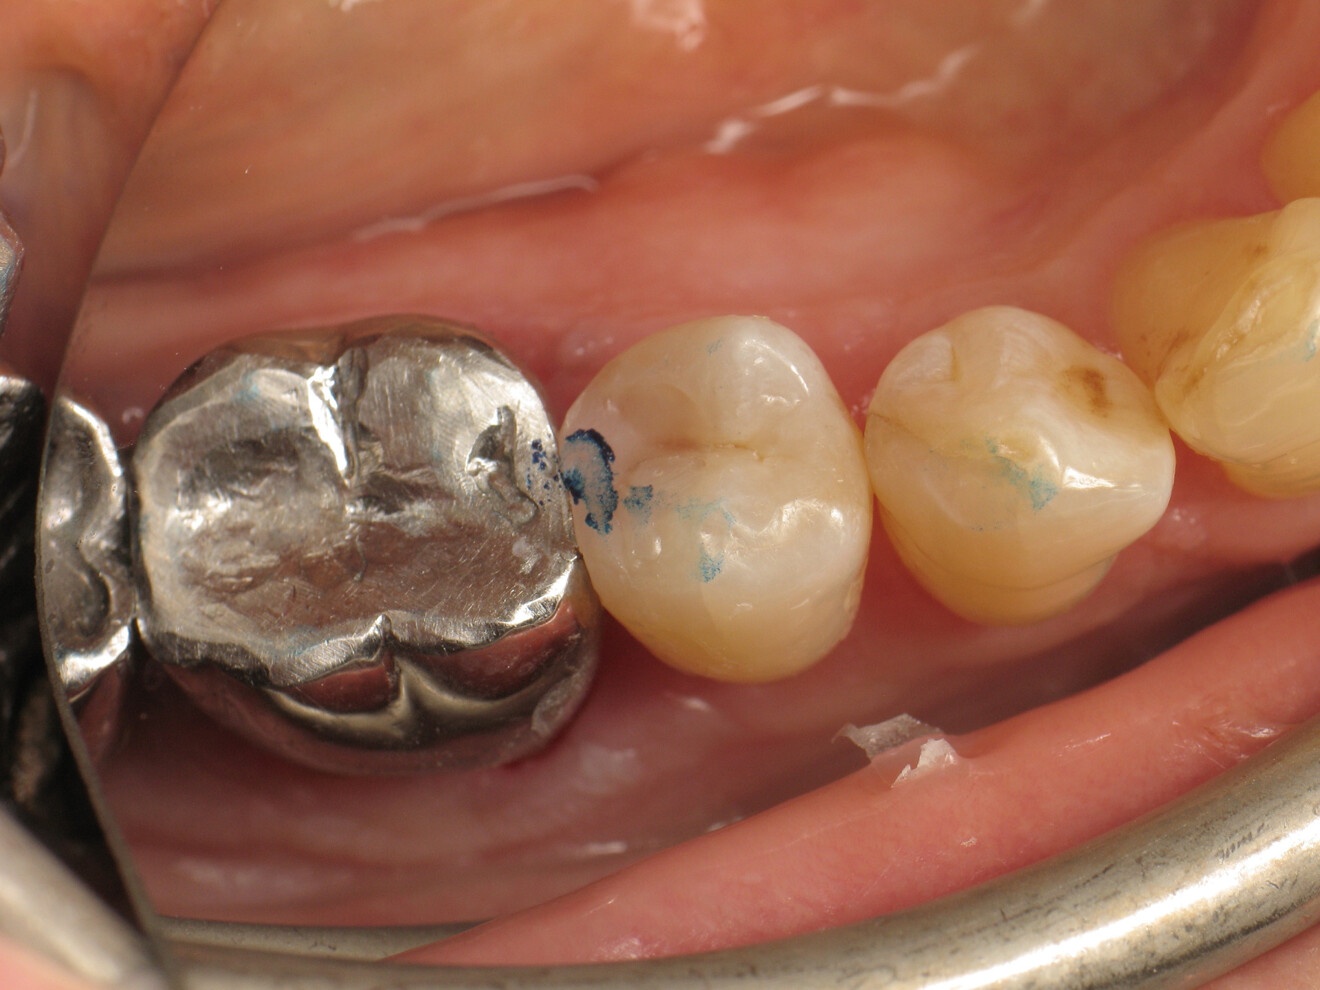

Fig. 20: Occlusion check before adjustments.

Fig. 21: Occlusion check after adjustments.